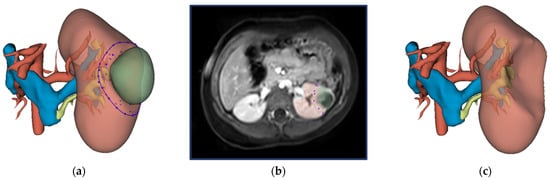

The surgical protocol for NSS consists of identifying the tumor with intraoperative ultrasound, followed by circumscribing the resection border with diathermy, and subsequent radical tumor removal [15]. The virtual resection was designed to mimic this surgical approach. The methodology for virtual resection is visualized in Figure 1. The surgeon was able to gain familiarity with the patient’s anatomy by inspecting the 3D visualization and the available imaging data beforehand. After inspection, resection started with the surgeon selecting several points on the surface of the kidney and the resection software computed a closed curve between these points. This closed curve is visualized with the purple line in Figure 1a and represents the circumscription of the resection border with diathermy. Secondly, the surgeon selected several intraparenchymal points in the available imaging data (shown in Figure 1b). Both the closed circle and intraparenchymal points were combined and used as input for the ResectionPlanner. This resulted in a 3D model of the virtual remnant kidney used for the computation of the virtual RRV shown in Figure 1c. Finally, the surgeon was able to perform small final corrections on the 3D model with tools available in 3D Slicer.

Figure 1. Workflow for virtual resection in 3D Slicer: (a) 3D visualization of the kidney, tumor, urinary collecting system, renal artery and renal veins. The closed curve as selected by the surgeon is indicated in purple. (b) Preoperative MRI imaging (post-contrast fat-suppressed T1-weighted) of the abdomen with the kidney and WT segmentation in red and green, respectively. The surgeon selected intraparenchymal points on this MRI scan. (c) 3D visualization of the virtual kidney volume after virtual resection.